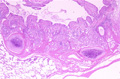

- 5.Lung, Pleura

- (6)Bronchial asthma

Macroscopic view: The cut lung surface from a patient with long standing bronchial asthma shows the compounding effects of chronic disease. The bronchial wall is thickened wall and the lumen is stenotic. The cut parenchymal surface is moist.